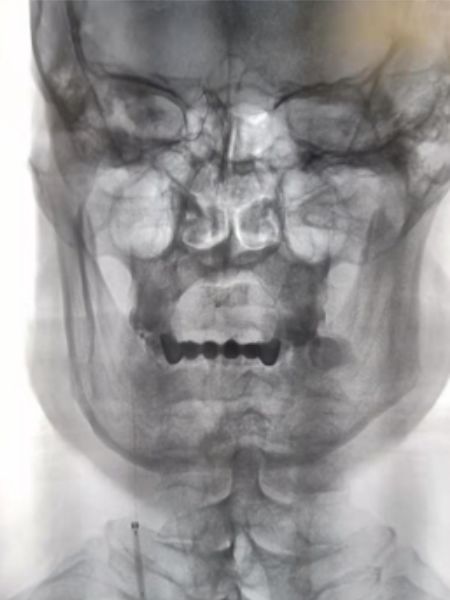

2019-05-24外院头颅MRI+MRA+DWI:右侧基底节区、放射冠、半卵圆中心脑梗死,右侧颈内动脉闭塞(图1)。

图1